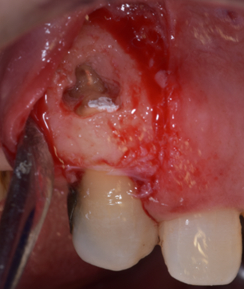

Second clinical case: fenestration of the apical third of the vestibular root of 14 diagnosed after endodontic treatment.

The second case: bone filling surgery, apical resection and retro filling, favorable outcome for two years.